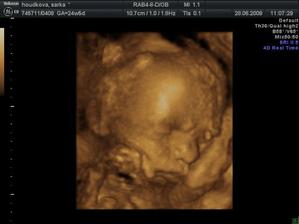

27.3 09 vyšetření screening dopdl dobře 🙂 miminko je zdravé má 11+5tt a 8cm žádná vývojová vada se nenašla. Jen placenta má rýhy jizvičky od hematomů,ale to prý nevadí to se zahojí.Hematomy už jsou pryč 🙂 28.5 Vyšetření a velký ultrazvuk ve 21tt dopadl dobře miminko zdravé vše bylo v pořádku , ukázal nám že to je kluk jako buk a váží už 413g .Také ve 21tt dává o sobě vědět už to není jen bublání v bříšku,ale semtam kopaneček a to tak dvakrát za den 🙂 4D ultrazvuk ve 25tt